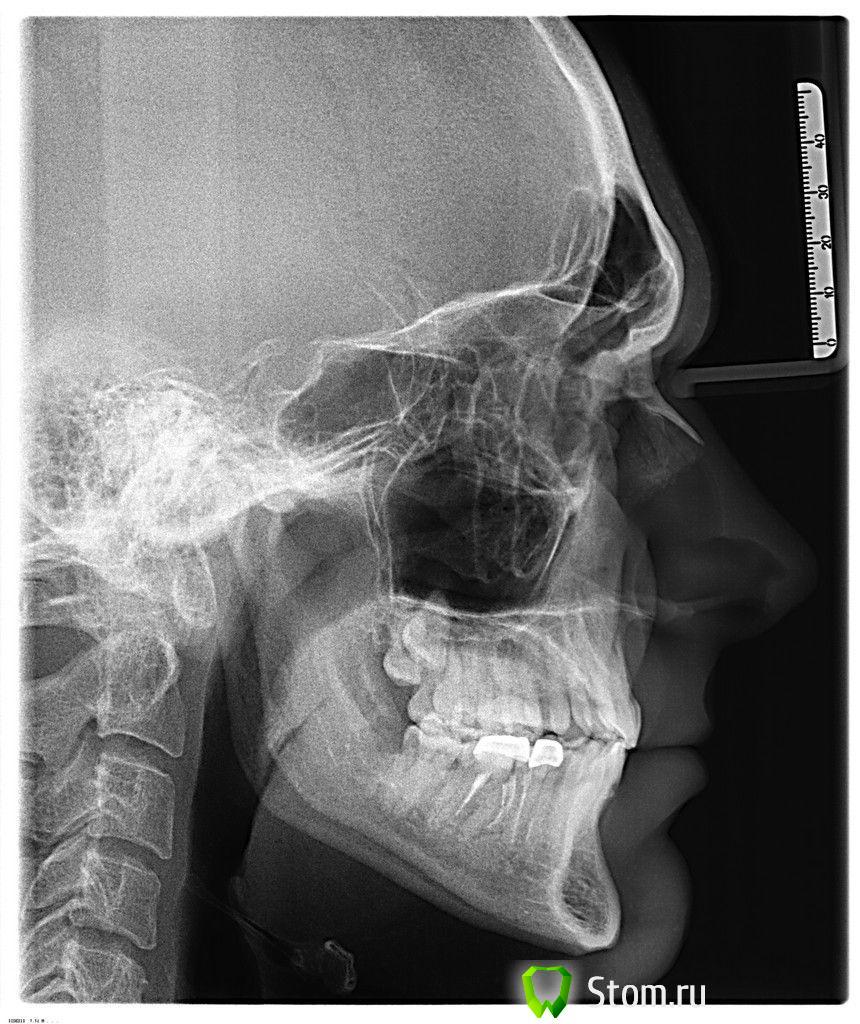

Oleg-Gru Опубликовано 24 ноября, 2011 Автор Поделиться Опубликовано 24 ноября, 2011 (изменено) дальше, сделал телерентгенограмму. что скажете, уважаемые специалисты? пациент совсем плох? Изменено 24 ноября, 2011 пользователем Oleg-Gru Ссылка на комментарий

Aldo Rain Опубликовано 24 ноября, 2011 Поделиться Опубликовано 24 ноября, 2011 http://s004.radikal.ru/i206/1111/09/3ff7a7cf45e8.jpg Одна из возможных причин стираемости передних зубов это то, что верхняя челюсть(линия ANS-PNS) имеет крен в сагиттальной плоскости, оценивается по соотношению линии ANS-PNS к Ba-ANSВо время глотания плоскость окклюзии(линия ANS-PNS) всегда стремится к выравниванию по горизонту(линия Ba-ANS всегда параллельна горизонту). Поэтому грубо говоря меняется положение головы во время глотания и задняя часть верхней челюсти(PNS) поднимается, это приводит к перегрузке передних зубов, они либо начинают стираться, либо уходят в протрузию.Это только одно обстоятельство. Далее необходимо провести анализ моделей челюстей в артикуляторе, чтобы определить положение верхней челюсти в пространстве, ибо от положения верх челюсти зависит положение нижней. Также необходим мониторинг движений ВНЧС на спец компьютерном оборудовании типа Zebris или др.кинезиографе, что позволит определить вид двнчс(интра или экстракапсулярные).Лечение следует начинать именно с ВНЧС, это 1 этап лечения, изготовление декомпрессионная сплинт-терапия.2 этап - ортодонтическое лечение3 этап протезирование на новой высоте прикуса. Ссылка на комментарий

Skip Опубликовано 24 ноября, 2011 Поделиться Опубликовано 24 ноября, 2011 Бруксизм.Вполне допускаю, по ТРГ похоже есть АР-травма, ниж. челюсть довольно сильно смещена. Ссылка на комментарий

Oleg-Gru Опубликовано 24 ноября, 2011 Автор Поделиться Опубликовано 24 ноября, 2011 Рентгенолог тоже обратила на это внимание. Асимметрия лица имеет место быть. Ссылка на комментарий